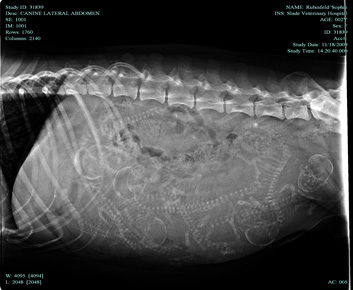

Two days before whelping, an X-ray shows that 7 puppies are about to be born. It's very crowded in there.